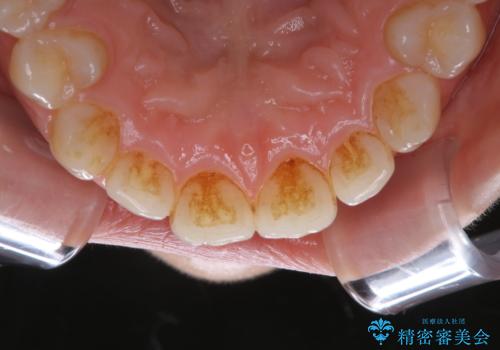

ワインによる着色・黄ばみをPMTCできれいに

- 前歯の着色・黄ばみを落としたい、とのことで来院されました。黄ばみや着色は前歯だけでなく、奥歯や裏表と全体的に付着していたため、PMTCの60分コースをご案内・ご相談し、行いました。